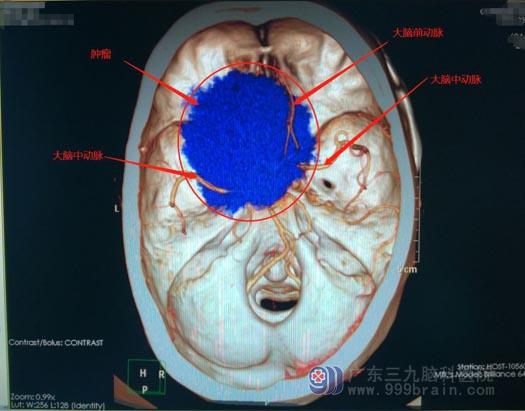

▲蔡某影像检查

蔡某在3月初来到了我院,入院时,他的左眼已经基本失明。我院头颅MR显示患者鞍结节偏左侧出现占位性病变,大小约为6.3cm*6.0cm*2.5cm;头颅CTA显示病变部分包绕双侧颈内动脉、双侧大脑前动脉、左侧大脑中动脉,其中双侧大脑前动脉及左侧大脑中动脉受肿瘤挤压,已经发生移位,这才导致蔡某左眼视力受影响。鲁明团队为患者实施了肿瘤切除手术。术后再经过一周的治疗,蔡某的左眼视力明显恢复,可以看清人脸。